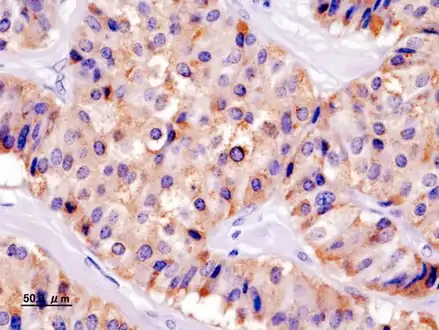

Pathology of pancreatic endocrine tumour (insulinoma). | |

- Pancreatic insulinoma

- Chromogranin A

- Insulin immunostain